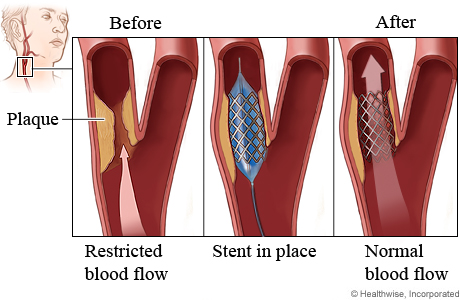

Carotid artery angioplasty and stenting: A widening of the arteries (angioplasty) to clear blood flow to the brain, then compressing the blockage against the artery wall using a stent – a small mesh tube – that reduces the chances of more narrowing or a blockage. (See illustration below.)